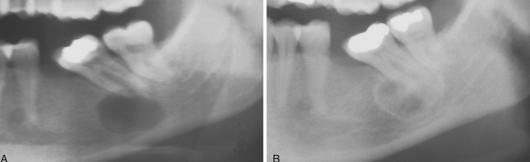

osteoblastoma

notice it is >2cm